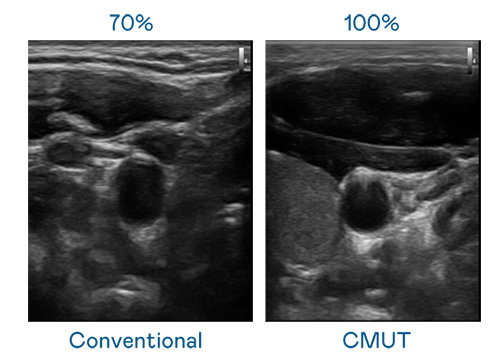

CMUT 技术是一种用电容式微机电元件来产生超音波讯号的技术。与传统 PZT 压电式技术相比,CMUT 频宽增加 30%,更宽频的超音波讯号让影像解析度大幅提升,是实现高影像品质医疗超音波扫描、促进精准医疗发展的关键技术。

大频宽带来超清晰影像

超音波影像的解析度高低,首先取决于探头能发出的讯号频宽。437ccm必赢国际 CMUT 可提供高清晰的超音波讯号,提供高频宽、高灵敏度、影像纹理细节更高的超音波影像,协助医护人员缩短影像判读时间及利用精准的医疗影像进行诊断。